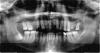

Nikk3 Опубликовано 14 мая, 2010 Поделиться Опубликовано 14 мая, 2010 Уважаемые стамотологи.Посоветуйте пож..что можно сделать в этой ситуации.На верхней челюсти 7, зуб подвижен и со сколом.Так сказали в клинике.Надо удалять.4 удалять.8 под вопросом..но там кариес и скол.1и6 тоже удалять.С номерами зубов ..может что и напутал.После предлагают поставить нейлоновый протез.Импланты ....говорят не мой случай т.к не кости.Но совсем не исключили(имплантацию). Ссылка на комментарий

Nikk3 Опубликовано 16 мая, 2010 Автор Поделиться Опубликовано 16 мая, 2010 Самое простое мостом 13-25 и замковый бюгель + поработать с нижним зубным рядом.Это относительно быстрое и бюджетное решение.Тем не менее эстетика будет вполне удовлетворительная. Можно решить вопрос имплантами-дольше, много дороже, много замороченнее, но тоже решаемо. Мостом 13-25 и замковый бюгель + поработать с нижним зубным рядом.Какие зубы при этом надо удалять.А какие оставлять?И что с низом..делать?Спасибо. Ссылка на комментарий

Nikk3 Опубликовано 16 мая, 2010 Автор Поделиться Опубликовано 16 мая, 2010 удалять все, что не входит в линию между 13-м и 25-м, это же очевидно.А с низом..оптимизировать окклюзию выборочно ставя одиночные коронки.Это значит,депульпировать и обтачивать линию между 13-м и 25-м.Мне не оч. хотелось-бы это делать.Может есть еще варианты?Спасибо за ответы. Ссылка на комментарий